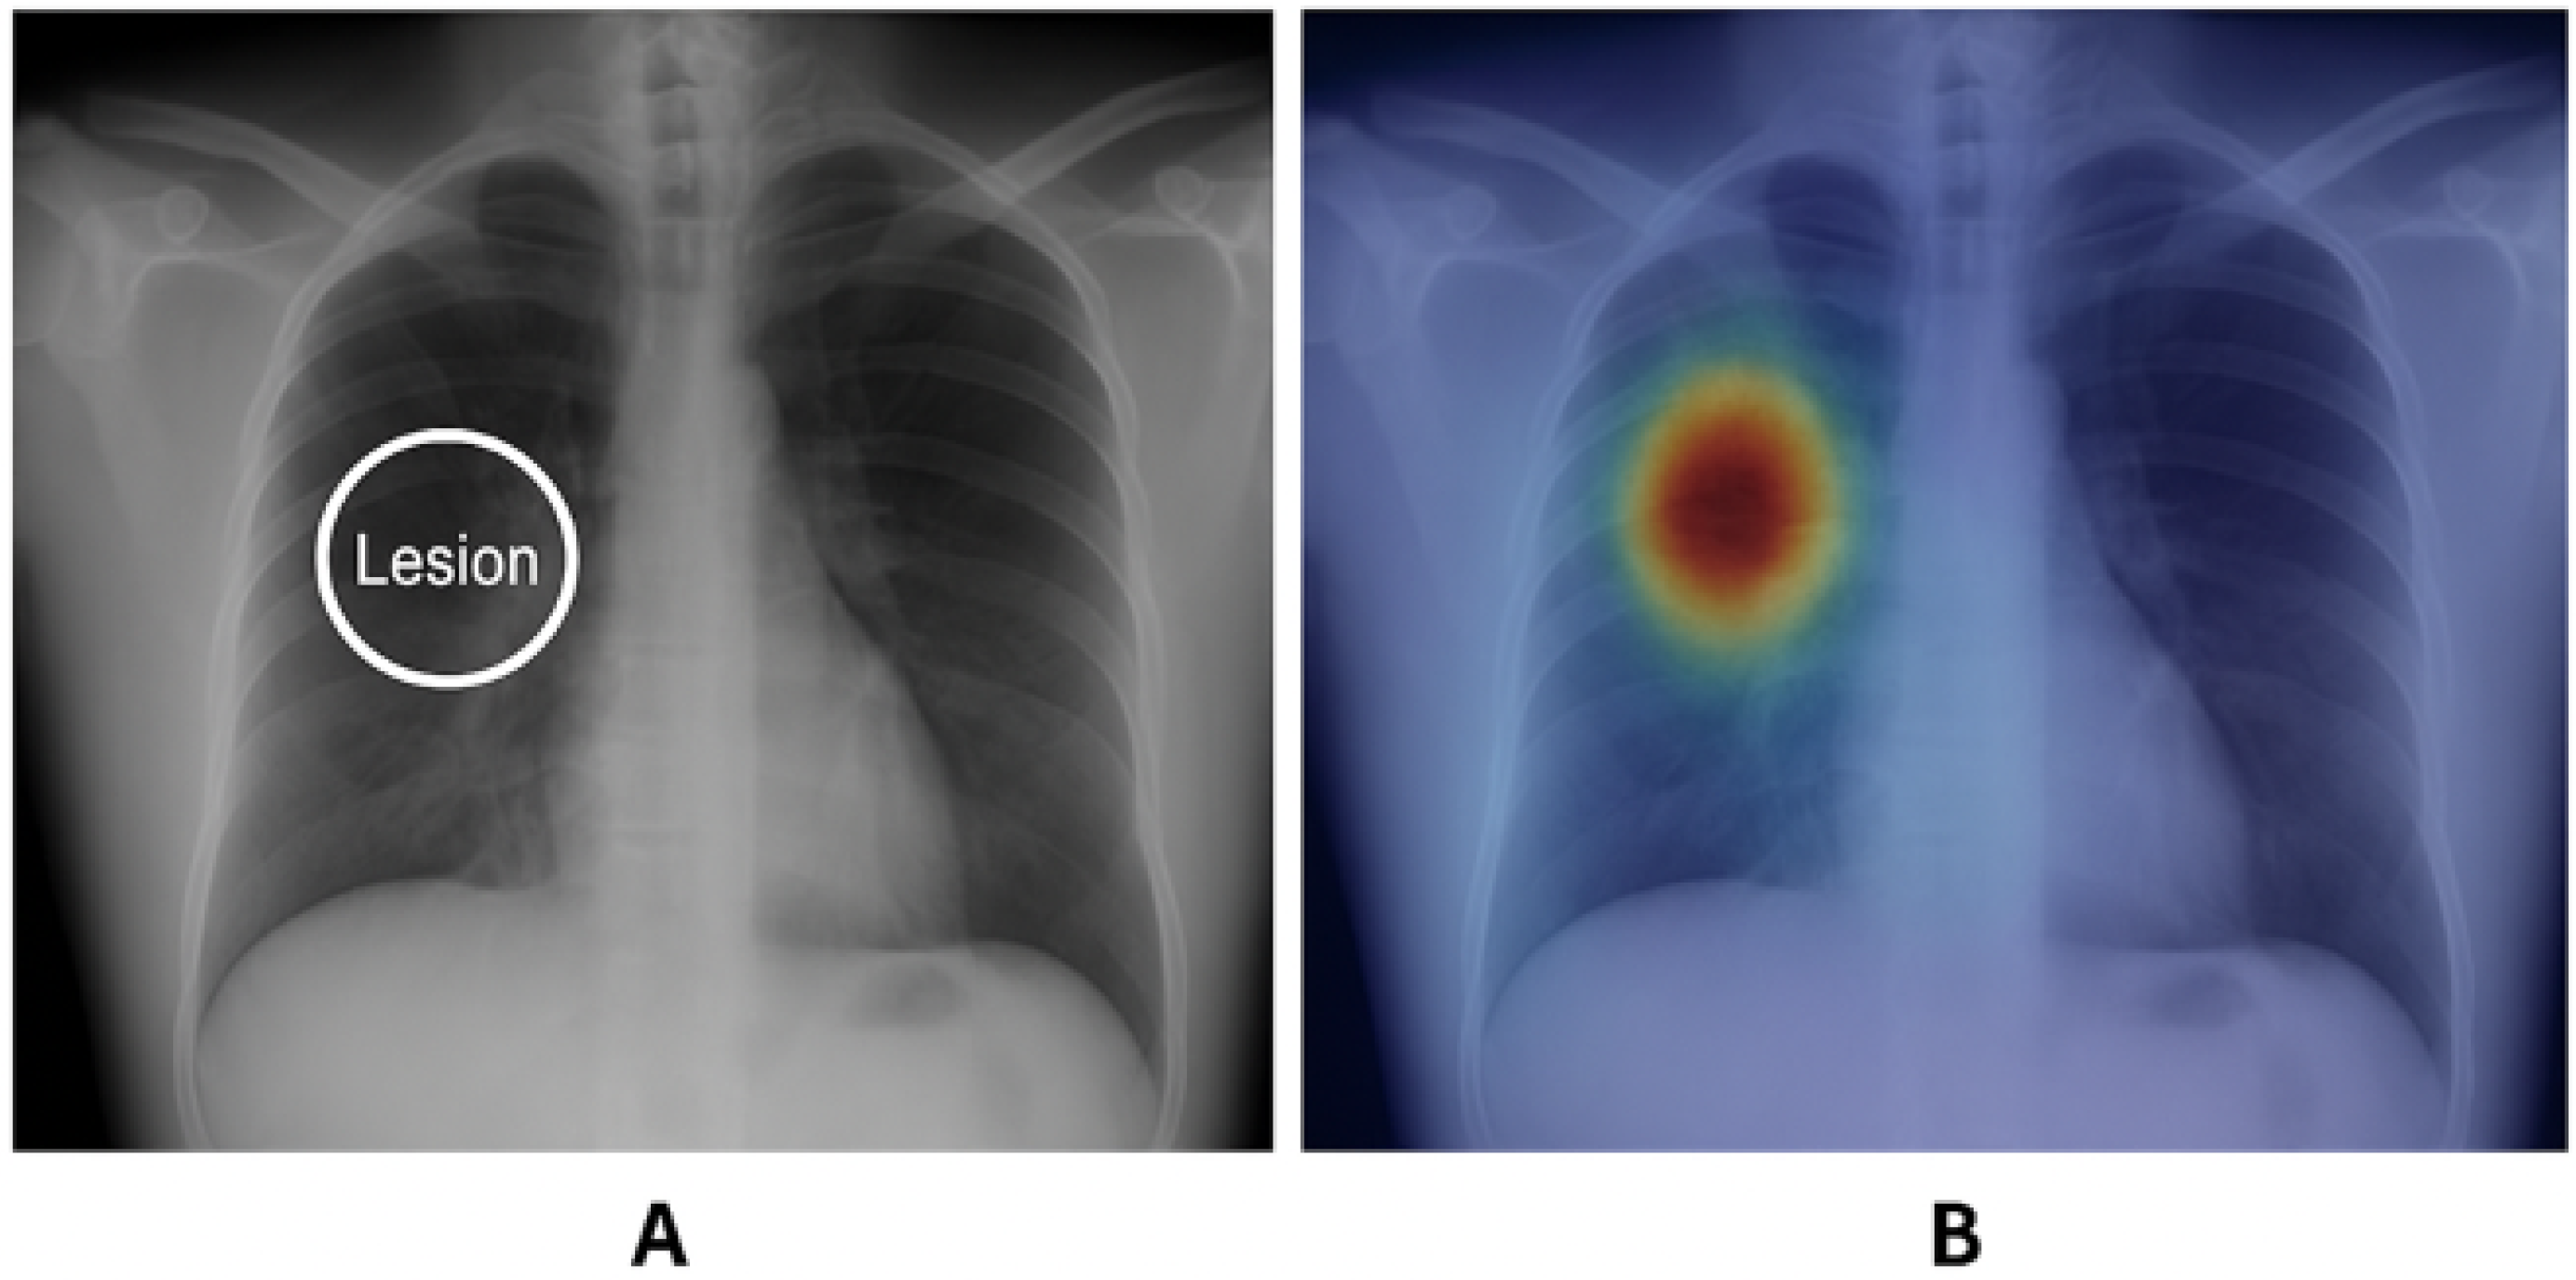

- Medical Imaging Overlap: In medical datasets such as CheXpert, Intersection over Union (IoU) is used to quantify the overlap between saliency maps and disease regions.

- CheXpert and NIH ChestX-ray14 for medical imaging, emphasizing pixel-level diagnostic localization.

- Medical imaging requires high-resolution, spatially accurate maps to support diagnostic decision-making.

- Transformer-based XAI achieves the highest IoU (0.090), making it most effective in medical imaging applications.

- RISE (0.045 IoU) performs better than Grad-CAM and SmoothGrad but at high computational cost.

- Grad-CAM (0.027 IoU) and SmoothGrad (0.021 IoU) struggle in aligning with expert annotations.